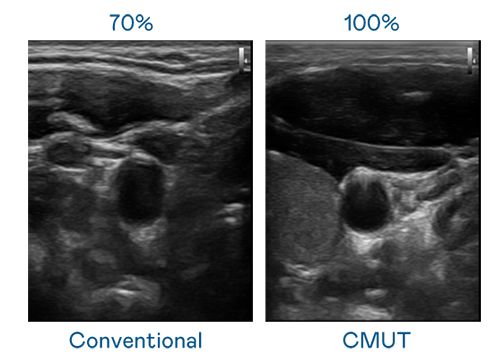

CMUT 技术是一种用电容式微机电元件来产生超音波讯号的技术。与传统 PZT 压电式技术相比,CMUT 频宽增加 30%,更宽频的超音波讯号让影像解析度大幅提升,是实现高影像品质医疗超音波扫描、促进精准医疗发展的关键技术。

大频宽带来超清晰影像

超音波影像的解析度高低,首先取决于探头能发出的讯号频宽。BJL平台 CMUT 可提供高清晰的超音波讯号,提供高频宽、高灵敏度、影像纹理细节更高的超音波影像,协助医护人员缩短影像判读时间及利用精准的医疗影像进行诊断。